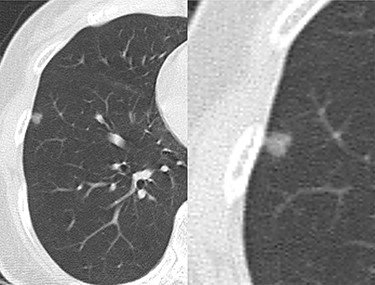

A never-smoker woman in her 50s with unremarkable family and medical history was referred to our department by a dermatologist to treat a lung nodule following a history of rapidly growing brown-to-black spots with mild pruritus, mainly on her trunk (Fig. 1). Histopathologic analysis was consistent with SK. To rule out the possibility of LTS, the patient was evaluated for potential internal malignancies. Computed tomography (CT) revealed a 0.6-cm pure GGN in the right lower lobe (RLL) (Fig. 2). There were no other malignant findings on CT, esophagogastroduodenoscopy, colonoscopy or ultrasonography for breasts and thyroid. All tumor markers examined were within the normal limits.

Computed tomography (CT) shows a ground-glass nodule in the right lower lobe.